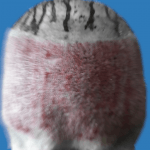

QUAIS SÃO AS POSSIVEIS COMPLICAÇÕES

DAS CIRÚRGICAS ILÍCITAS?

| INFEÇÕES TERRÍVEIS | COMPLICAÇÕES QUE PÕEM A VIDA EM RISCO | RESULTADOS HORRÍVEIS |